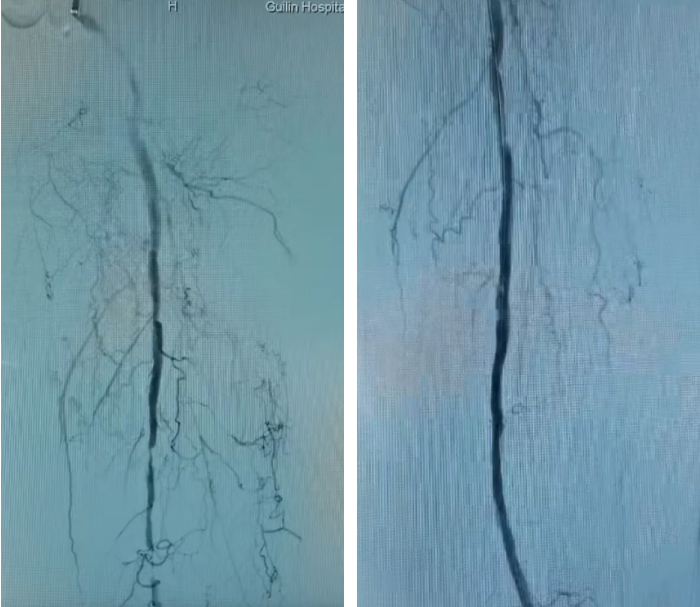

IVUS引导下的准分子激光斑块消蚀术中影像

股浅动脉长段闭塞段术前(左)血流中断,术后(右)真腔成功开通